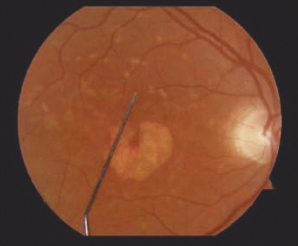

En el estudio se evaluaron a 15 pacientes, 7 con enfermedad de Stargardt, 1 con maculopatía en ojo de buey, 5 con DMAE, 1 con distrofia macular viteliforme de Best y 1 con distrofia de patrón. Todos los ojos examinados tenían áreas de autofluorescencia anormal del fondo. El PRL fue evaluado con fotografía de fondo y el microperímetro Nidek, este último midiendo también la sensibilidad del campo visual.

De los 15 ojos, 4 tenían fijación foveal y 11 tenían excéntrica. Los PRL excéntricos estaban por encima de la lesión atrófica y su estabilidad no dependía del grado de excentricidad de la fóvea. Además, la sensibilidad visual disminuyó notablemente en las localizaciones correspondientes a las áreas hipofluorescentes. No se redujo en las áreas hiperfluorescentes correspondientes a las manchas, pero sí la hiperfluorescencia que se encontraba en forma de anillos densos.

En conclusión, los PRL excéntricos se encontraban en la retina superior en regiones de autofluorescencia normal del fondo. Además, la estabilidad de fijación no se correlacionó con el grado de excentricidad de la fóvea. Por ello, hay que tener en cuenta que para evaluar los resultados de los ensayos de tratamiento es fundamental utilizar métodos que relacionan la morfología de la retina con la función visual.